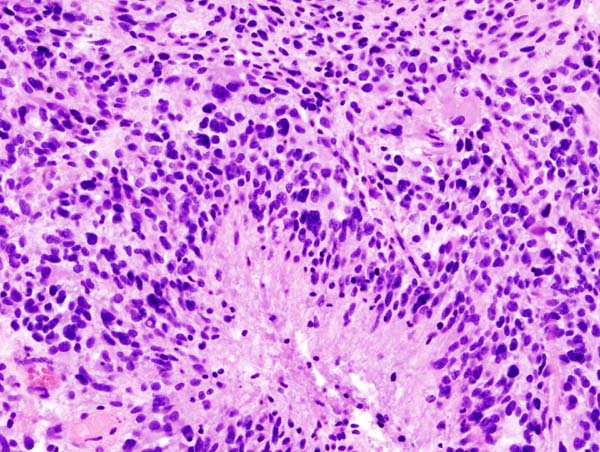

The histology of medulloblastomas shows small, rounded blue cells are visible on histology, and Homer-Wright rosettes might be present.